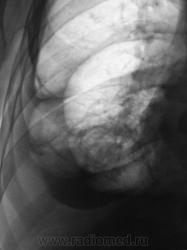

Множественные осумкования в правой плевральной полости жидкости и газа - эмпиема.

Из очевидного - частично осумкованный правосторонний гидроторакс. Неясно, почему правое легкое как бы поддавливает правый контур срединной тени. Нарушение бронхиальной проходимости, клапанная эмфизема? Пациент нуждается в дообследовании.

Конечно же посмотрел бы пациента на УЗД. Больше данных за эмпиему правой плевральной полости.